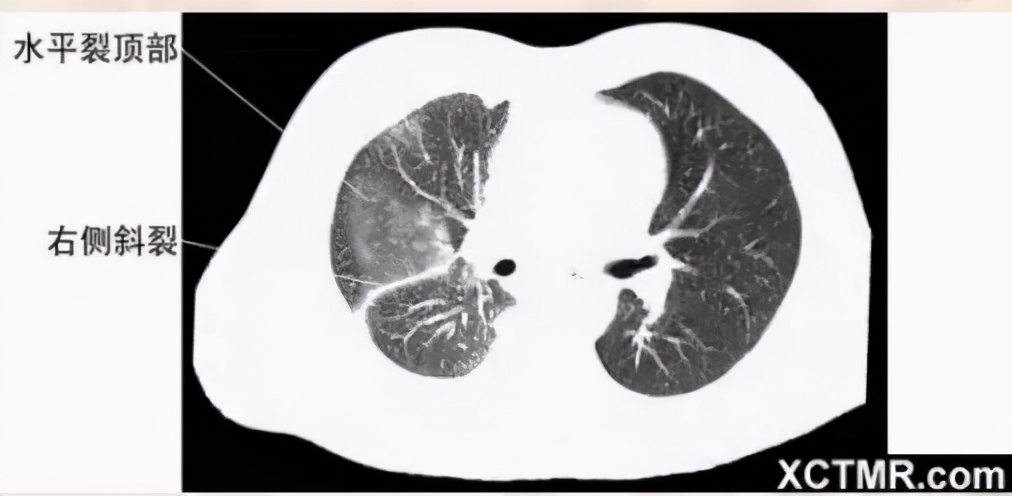

肺窗